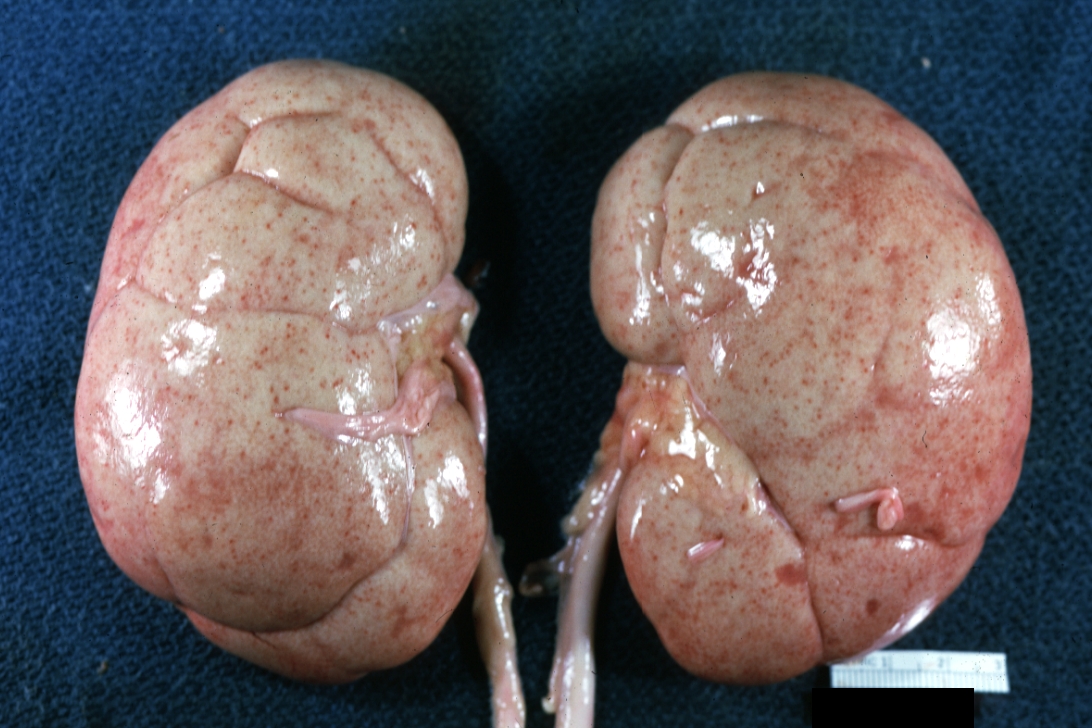

GROSS: Urinary: Kidney: Lupus Erythematosus: Gross enlarged very pale kidneys with flea bite or ectasia good example of kidneys from someone with nephrotic syndrome or subacute glomerulonephritis